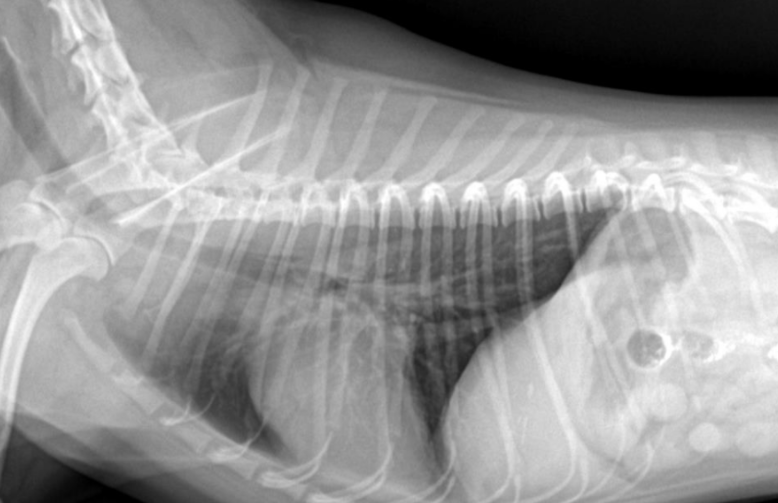

์ํ์ฅ : GD vs. GDV

- ๊ฐ๋ณ์ key point๋ pylorus์ ์์น & ์์ ๋ถํํ(compartmentalization) !

- ์ ์์ ์ธ ์์น๋ ์ธ์ธก์์์ ์๋์ชฝ, ๋ณต๋ฐฐ์์์ ์ผ์ชฝ์ ์์น.

- GD๋ ์๊ฐ ํ์ฅ๋์ด ์์ผ๋, ์์น๋ ๊ทธ๋๋ก.

- GDV๋ ์ฅ์ด ๊ผฌ์ด๋ฉด์ ์์น๊ฐ ๋ฌ๋ผ์ง๋ฏ๋ก, pylorus์ ์์น๊ฐ ์ธ์ธก์์์ ์์ชฝ

| GD | GDV | |

|---|---|---|

| VD | - greater curvature ์ผ์ชฝ(์ ์) * 360๋ ํ์ ์์๋ ์ผ์ชฝ์ ์์น | - greater curvature ์ค๋ฅธ์ชฝ (180๋ ์ผ์ ) - duodenum ์์น๋ ํจ๊ป ๊ผฌ์ |

| RL | - pylorus๊ฐ ์๋์ชฝ(์ ์) | - pylorus ์์ชฝ - ์์ ๋ถํํ(compartmentalization) : ๋ถ๋ฐฉ ํ์ธ - gastric band (soft tissue) ๊ด์ฐฐ |

![]() ![]() | ![]() ![]() | |

[๋ถํํ]![]() ![]() |